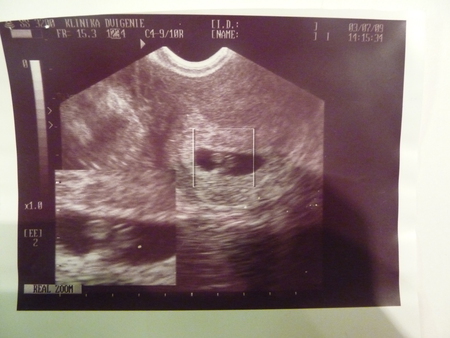

НЕ ПЕРВЫЙ малышНачалось все с того. что я пошла удостовериться что я беременна. Вот каким он был на 7-ой недельке

Тут он 27 мм, такой маленький......